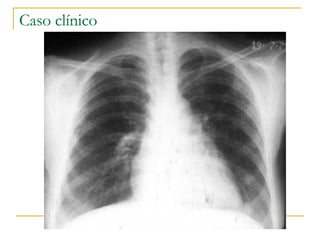

CASO CLINICO Paciente de 27 años, sexo masculino, no fumador, sin antecedentes patológicos importantes para destacar, que en la semana previa a la consulta presentó rinitis y tos seca, acompañados de mialgias, cefalea y fiebre. Se automedicó con antipiréticos y permaneció 3 días en cama. Dos días antes de su ser internado en el hospital había agregado expectoración mucopurulenta y hemática y dolor en hemitórax derecho. Desde el inicio de sus síntomas tuvo anorexia y fatigabilidad fácil.

Del examen físico se destacó: Tº axilar de 39º C, FR 28 p/m, soplo tubario en tercio superior de cara posterior de hemitórax derecho, taquicardia regular de 112 p/m.  En la radiografía de tórax se observó una opacidad densa homogénea de hemitórax derecho limitada en su borde inferior por la cisura horizontal.